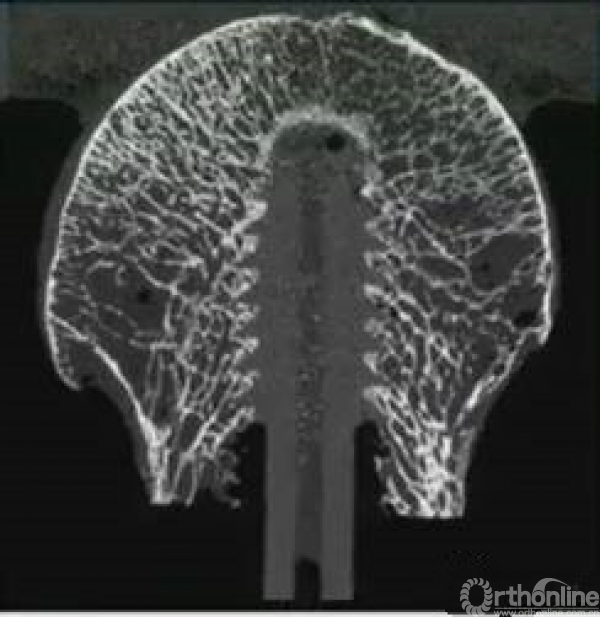

骨质疏松也会影响内固定在股骨头内的稳定性。

疏松的骨质不适合使用螺钉稳定,而更适合螺旋刀片打压。

同时,双钉可以更好的预防头钉切出。